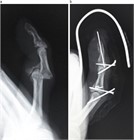

1. 指が物にぶつかって受傷するいわゆる「突き指」には、骨折や靭帯損傷など重度の損傷が隠れている場合がある。

1. 注意深い診察とX線写真撮影により、損傷に応じた適切な治療を行うことが推奨される。